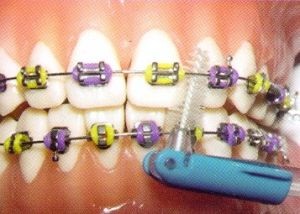

- După fiecare masă dinții trebuie să fie curățate cu grijă. Pentru aceasta există instrumente ortodontice speciale.

- Ai nevoie să se spele pe dinti potrivite numai pentru duritate perie. Cea mai bună perie potrivită cu mediu greu.

- Trebuie avut grijă pentru a nu deteriora aparatul în timpul curățării. Acest lucru este valabil mai ales de arce de metal.